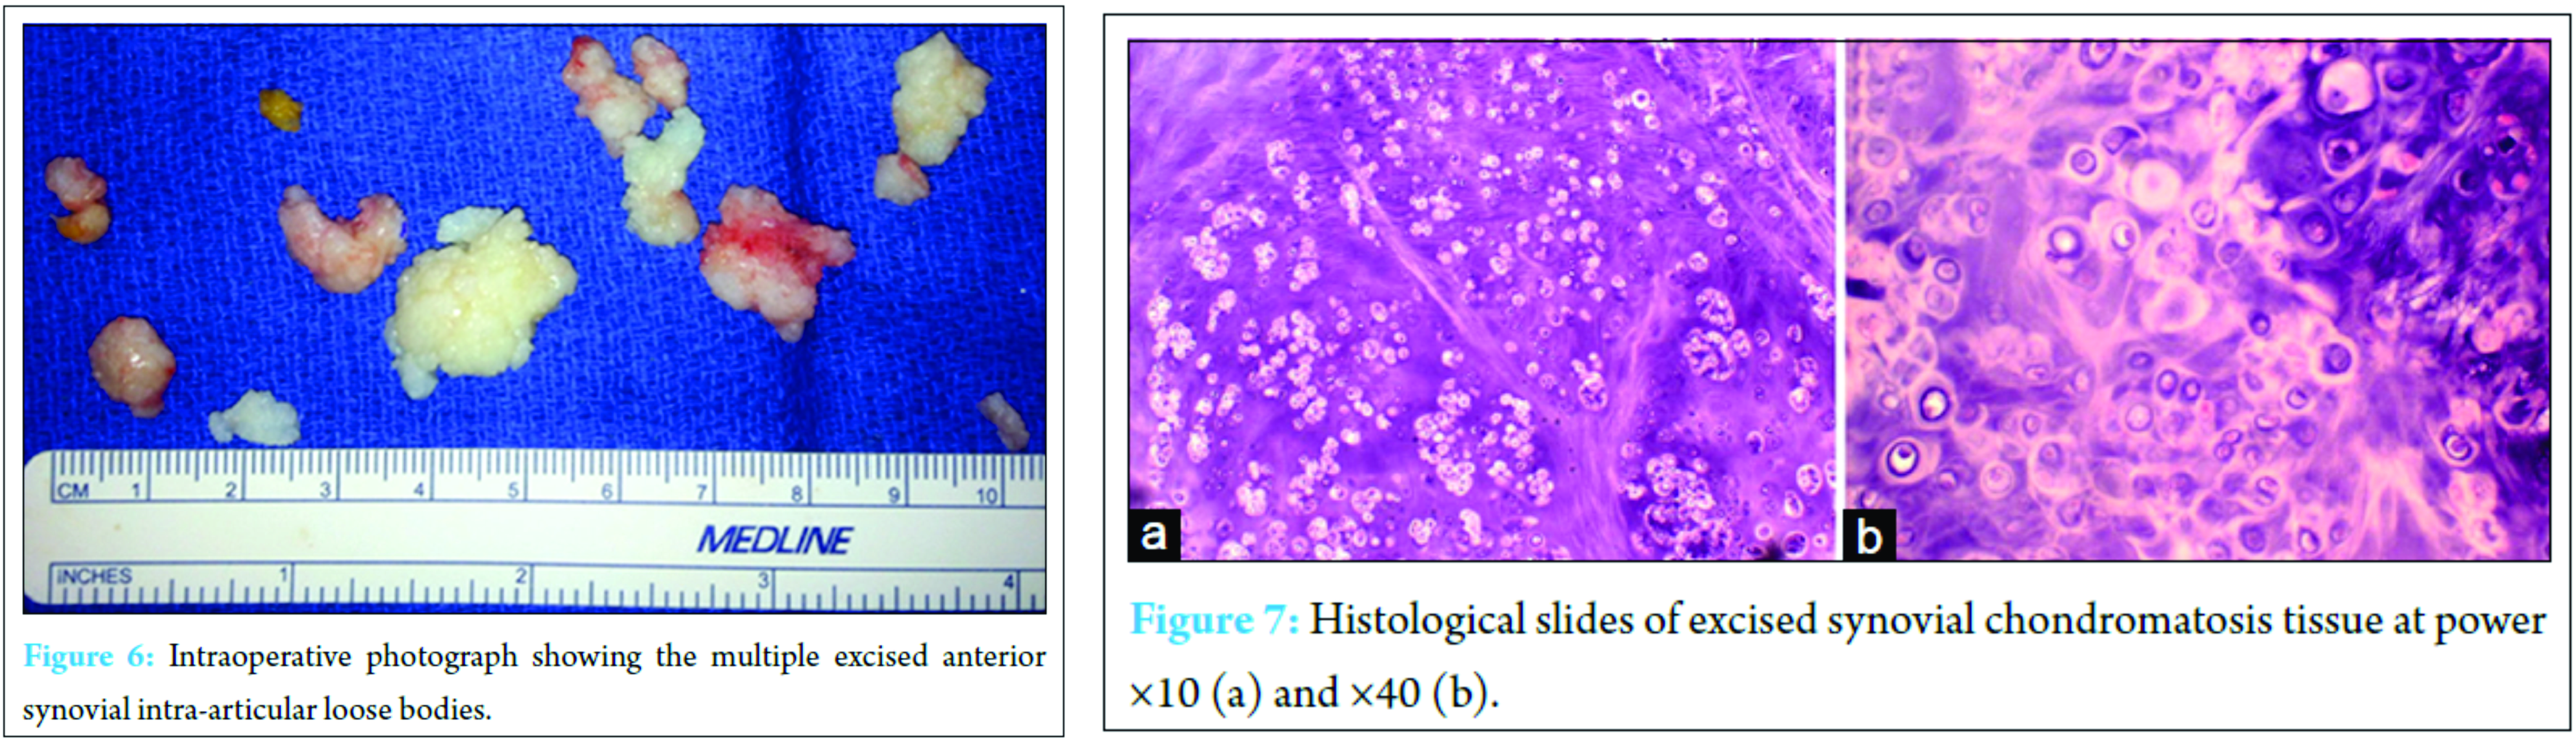

The patient was prepped and draped in the usual sterile fashion. Portals were established into the ankle joint anteromedially and anterolaterally with transillumination positioned lateral to the branch of the superficial peroneal nerve. On entry into the joint space, a considerable amount of scar tissue formation and tissue inflammation was appreciated. A thorough debridement was performed using a 2.7 mm scope and a 3.5 mm protected aggressive shaver. All chondromatosis tissue was visualized Fig. 5a and b; however, to remove all of the intra-articular loose bodies and debris, the anterolateral portal incision was extended by 0.5 cm and the tissue was removed in a piecemeal fashion through the portal. Close attention was paid to avoid leaving any soft tissue debris in the intra-articular space or surrounding soft tissue. Attention was then focused on the posterior aspect of the ankle joint. A separate incision was made along the posterolateral aspect of the ankle joint in the interval between the peroneal tendons laterally and the FHL medially (Fig. 5c). The sural nerve was identified and protected. Multiple irregularly-shaped, tan to pink-white pieces of chondromatosis tissues were removed from the ankle joint. Tissue obtained from the anterior synovium measured 1.1 cm × 3.5 cm × 4.1 cm in aggregate, while tissue from the posterior synovium measured 1.3 cm × 3.5 cm × 5.1 cm in aggregate (Fig. 6). Recovered tissue was sent to the pathology laboratory with a return diagnosis of synovial chondromatosis without evidence of malignant transformation. Histologically, the tissue showed cartilaginous hyaline nodules with mild chondrocyte atypia and occasional mitoses (Fig. 7). Following surgery, the patient had complete resolution of symptoms including the tingling in the plantar aspect of his foot. At 3 years of follow-up, the patient remained asymptomatic without recurrence of symptoms.

The sural nerve was identified and protected. Multiple irregularly-shaped, tan to pink-white pieces of chondromatosis tissues were removed from the ankle joint. Tissue obtained from the anterior synovium measured 1.1 cm × 3.5 cm × 4.1 cm in aggregate, while tissue from the posterior synovium measured 1.3 cm × 3.5 cm × 5.1 cm in aggregate (Fig. 6). Recovered tissue was sent to the pathology laboratory with a return diagnosis of synovial chondromatosis without evidence of malignant transformation. Histologically, the tissue showed cartilaginous hyaline nodules with mild chondrocyte atypia and occasional mitoses (Fig. 7). Following surgery, the patient had complete resolution of symptoms including the tingling in the plantar aspect of his foot. At 3 years of follow-up, the patient remained asymptomatic without recurrence of symptoms.